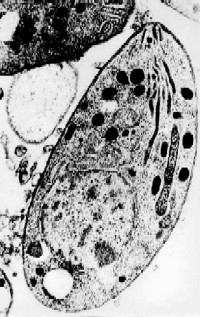

Toxoplasma gondii: left upper shows flagellates;

right upper: Toxoplasma in cardiomuscular tissue; lower: EM thin

section

Toxoplasma

gondii: A parasite in mammal muscular

tissues; ca. 60% of domestic cats are infected by Toxoplasma

-

Human

infection occurs but is of minor impact in

healthy people; babies and humans with immune deficiencies (AIDS) are prone

to Toxoplasmosis

Toxoplasmosis:

transfer from mother to unborn baby can result in mental retardation, blindness,

or death; AIDS patients may suffer severe brain damage leading to death